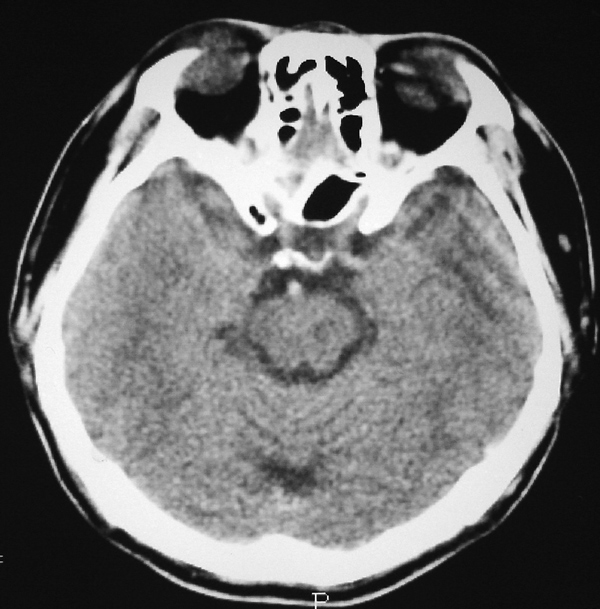

男 49岁 脑干腔隙梗塞5年。

这患者脑干(脑桥)腔隙脑梗塞是肯定的 有20002年资料 明天上传全部资料(当时工作忙 来不及)

图片质量不是很好!脑干偏左侧隐约可见低密度病灶,不知5年前怎样?单存本例支持:脑干梗塞!

1 单纯此图像定脑干梗塞依据不足. 2 可薄扫或核磁检查.

脑干中脑区的梗塞还是能诊断的,建议薄扫一下。或者mri检查

楼主是想具体分清是发生于脑桥还是中脑吧,脑桥的主要特征是结构就是小脑脚及四脑室,可以看到小脑脚及四脑室时就肯定是脑桥,中脑的主要特征就是环池,有完整的环池就是中脑,并且由于中脑短,一般只有一层可见,最多出现两层,本例层面应该是属于中脑层面,其上方应该是四叠体池及丘脑下部了.

楼主是想具体分清是发生于脑桥还是中脑吧,脑桥的主要特征是结构就是小脑脚及四脑室,可以看到小脑脚及四脑室时就肯定是脑桥,中脑的主要特征就是环池,有完整的环池就是中脑,并且由于中脑短,一般只有一层可见,最多出现两层。

不知小脑脚交叉到底另何指?中脑的病灶,应该和中脑导水管加以区别。

脑干梗塞在ct上是斑点状低密度,一般只能在桥脑或中脑才能显示,延髓是很难发现(伪影多)。mr上脑干梗塞应该是长t1长t2的斑点状表现。弥散能够发现早期梗塞灶,表现高信号。

3、在ct图片上怎样区别脑桥和中脑?

有三个主要标志:

①四脑室,脑桥平面有四脑室,中脑没有;

②环池:中脑平面有完整的环池,即前有脚间池、后有四叠体池。这是标准的om线扫描图像,如果不按om线扫描就有所变化;而桥脑没有完整环池,它前方是桥前池。

③三脑室,只要扫描基线偏移不大,看到三脑室出来同层面应该是中脑

本例脑干是不是梗塞?需要量进一步证实;

1、可用薄层扫描,如还有证实是梗塞;

2、薄层+增强效果会更好;

3、mri。